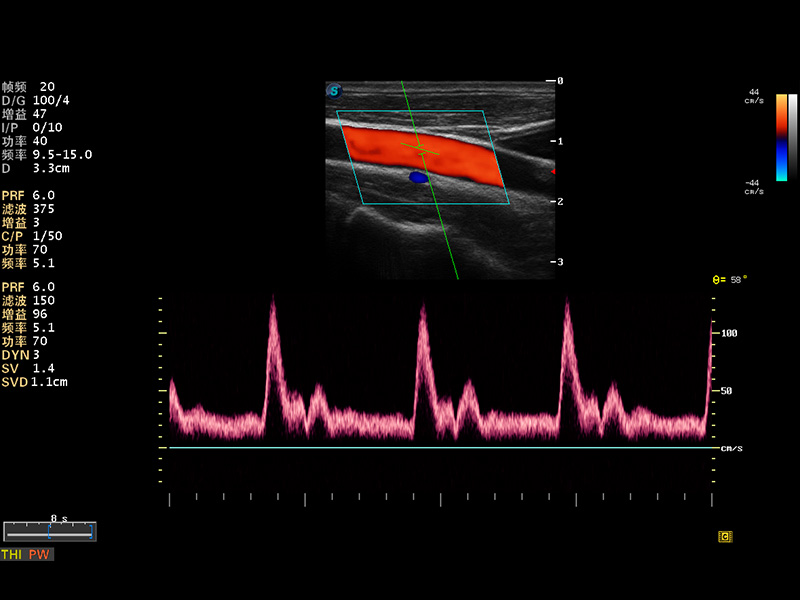

S8 EXP便携式彩色多普勒超声诊断仪是玖鼎集团研发的高端全身应用型便携彩超。高通道的VIS平台融合可视化(Visual)、智能化(Intelligent)和人性化(Smart)的特点,配以玖鼎集团自主研发生产的探头大家族,使您能够快速、准确的获得病人信息,提高工作效率的同时减轻疲劳。

μ-Scan微米成像

实时宽景成像